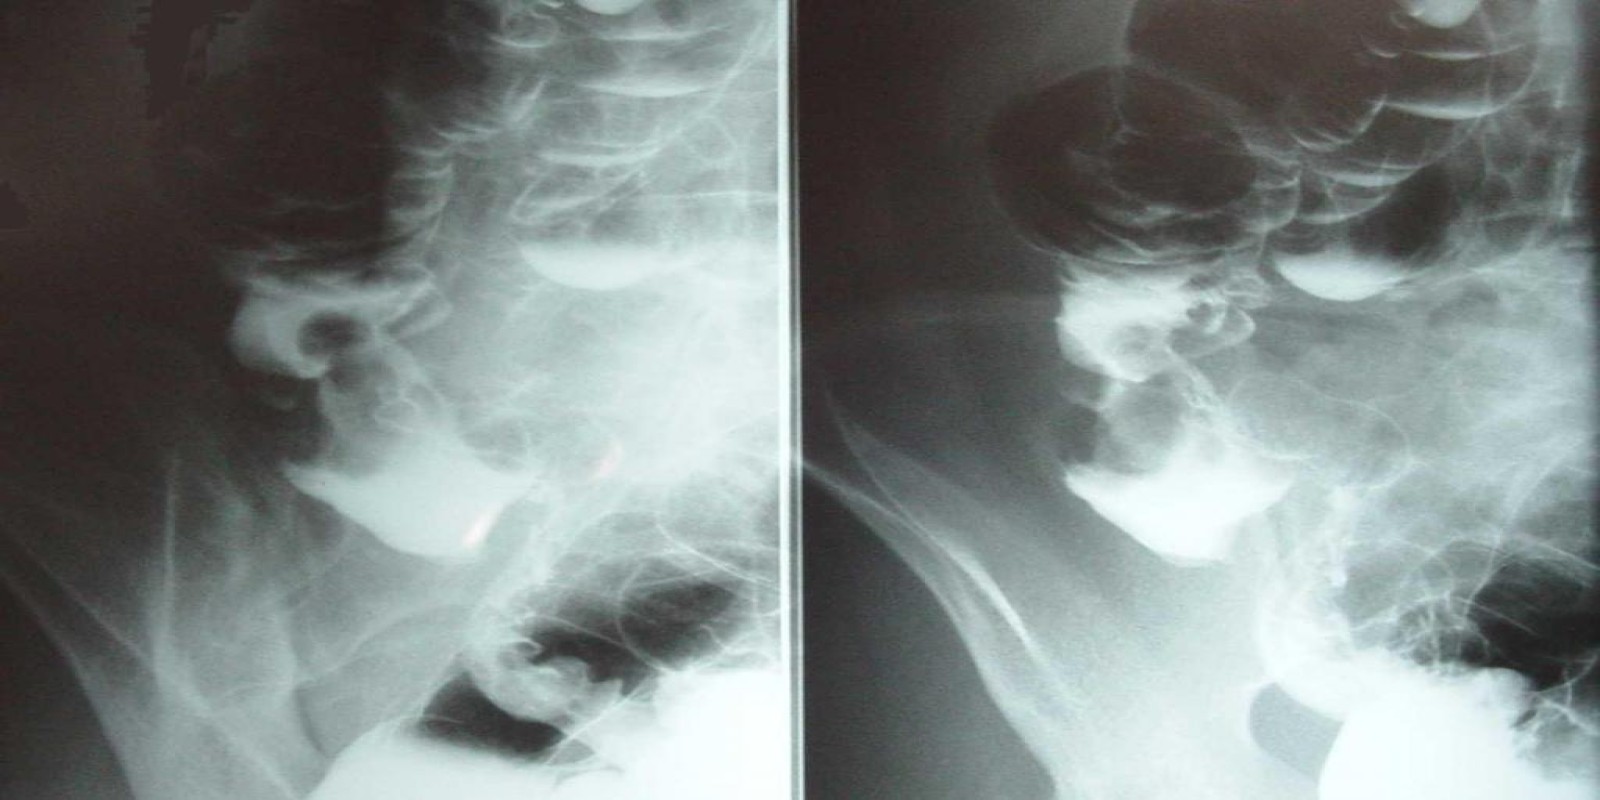

Caso Código 013A de Câncer do Cólon

Cod.: 013A